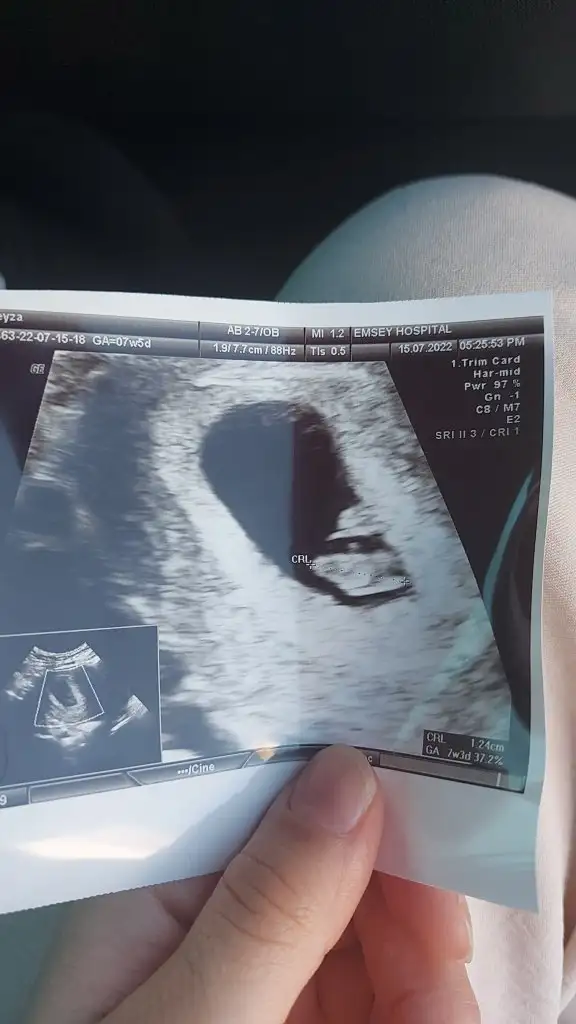

Altakki 8 haftalik

8+3 günlük tahminde bulunur musun canımvallahi atlamışımsenin prenses gibi canım öğrenince haberlerini bekliyorum